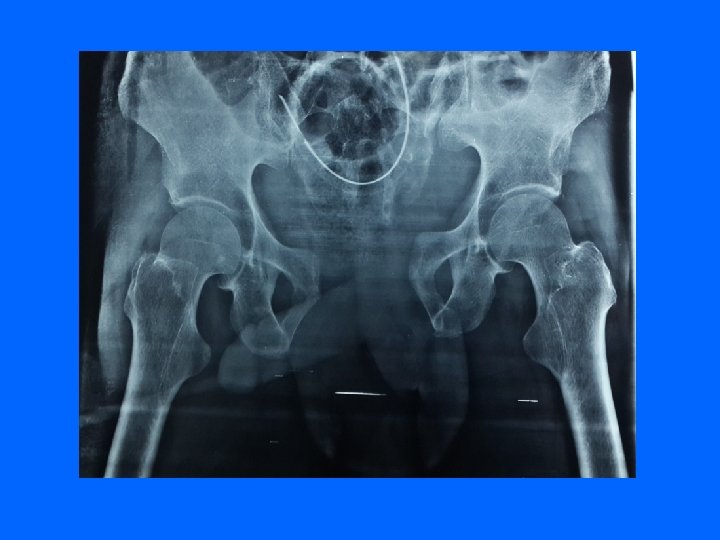

scanner Apporte des renseignements sur l'état des structures postérieures

Fracture de la sacro-iliaque

V) L'EVOLUTION DES FRACTURES DU BASSIN • Elle dépend des complications viscérales et vasculaires. • Sur le plan orthopédique, l'évolution est en général favorable en 2 mois. • Les cals vicieux sont en général bien supportés mais les disjonctions sacro-iliaques et pubiennes peuvent laisser persister des douleurs chroniques. • Le raccourcissement d'un membre inférieur peut être lié à une disjonction mal réduite. • Des complications obstétricales ultérieures peuvent se voir chez la femme. • Le retrecissement de l’uretre, l’incontinance urinaire et l’impuissance peuvent ce voir • Paralysie totale ou partielle